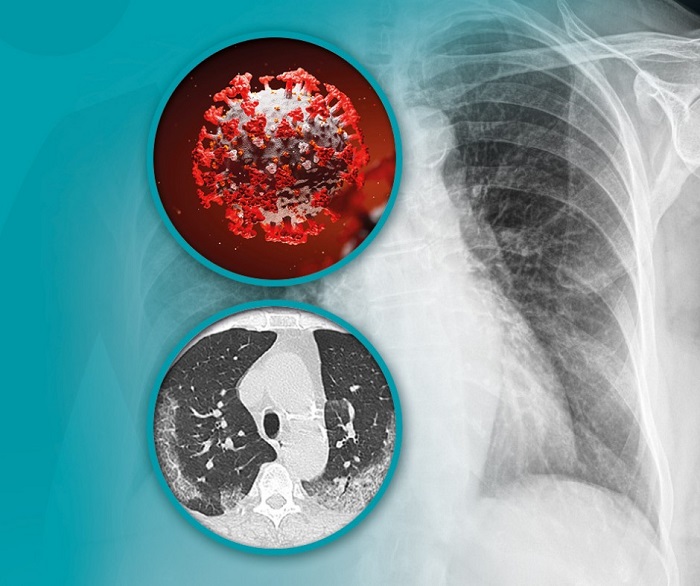

Pokazalo se da su pluća jedan od najugroženijih organa kod pacijenata koji boluju od kovida, a jedan od najpouzdanijih načina za detekciju promena nastalih pod uticajem ove bolesti su savremeni CT skeneri. Uz korišćenje veštačke inteligencije prilikom postavljanja dijagnoze, ovo su jedini uređaji za snimanje pluća koji mogu pouzdano da detektuju ne samo aktivne promene, već i posledice nakon preležane bolesti.

U tome što CT skener detektuje promene koje se na drugim dijagnostičkim modalitetima ne mogu prikazati. Ovo se naročito odnosi na tromboze u krvnim sudovima, sa posebnim akcentom na trombozu plućnih arterija, karakterističnih za osobe koje su razvile ove probleme kao posledicu kovid infekcije.

Multidetektorski CT skeneri su jedini uređaji za snimanje pluća koji mogu pouzdano da detektuju ne samo aktivne promene, već i posledice nakon preležane bolesti. Pored toga, ova tehnologija nudi mogućnost snimanja pluća sa presecima na jedan milimetar, što značajno doprinosi detektovanju svega što može da bude važno, kako za pacijente sa aktivnom kovid infekcijom, tako i za one koji su u međuvremenu ozdravili.

Pacijentima je takođe na raspolaganju i poseban program za veštačku inteligenciju RADLogics, koji omogućava obradu snimaka dobijenih na skeneru. Ovaj oblik veštačke inteligencije, potpuno objektivno, precizno i sigurno otkriva promene na plućima karakteristične za COVID 19 infekciju.